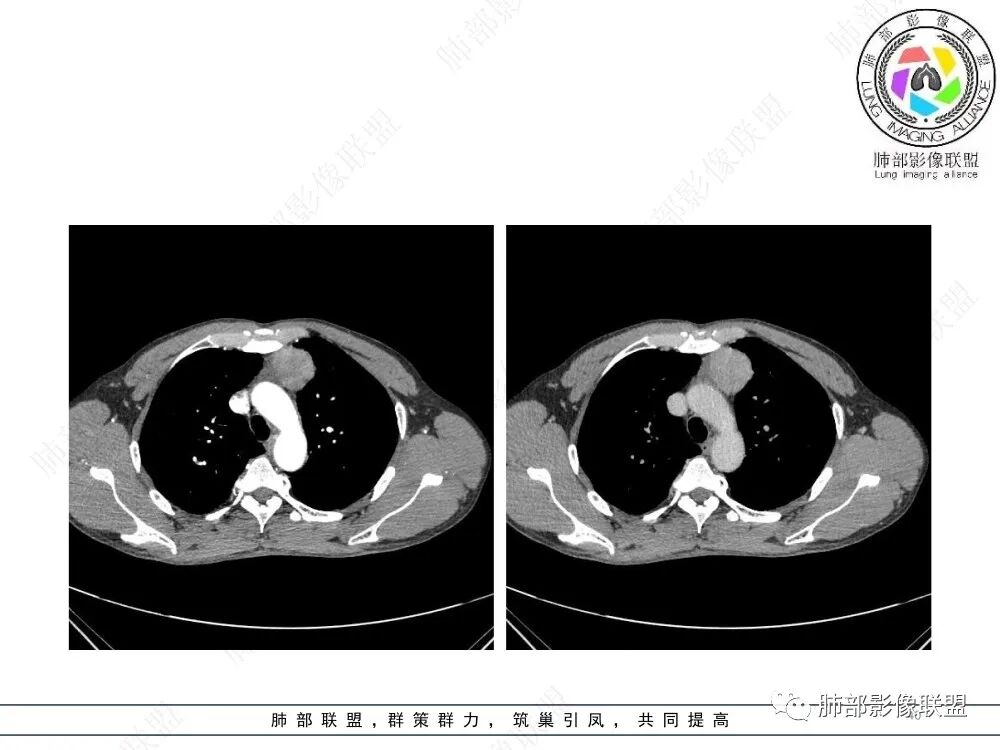

2、影像特点:前纵隔偏左侧软组织影,密度相对均匀,未见明显包膜钙化及实质内钙化,局部边缘浅分叶,周围脂肪间隙密度增高、浑浊,未见侵犯大血管、未见纵隔内淋巴结转移、未见侵犯心包内结构、未见胸膜转移结节、未见肿块沿着纵隔胸膜蔓延,未见胸腔积液。增强后动脉期不均匀强化,未见明显纤维分隔。

3、 病 例 小 结:40岁以上,前纵隔偏侧性生长的肿块,常规考虑胸腺瘤。难点就在于胸腺瘤的分型。但是对于前纵隔占位影像诊断的关键在于区分胸腺囊肿、胸腺瘤、胸腺癌及其他恶性肿瘤。至于胸腺瘤,主要在于判断有无侵袭性。

胸腺瘤(thymoma)是最常见的前上纵隔原发性肿瘤,约占成人所有纵隔肿瘤的20%~40%,它起源于胸腺上皮,但不包括起源于生殖细胞、淋巴细胞、神经内分泌细胞及脂肪组织的肿瘤。绝大多数胸腺瘤位于前纵隔,附着于心包,与纵隔内大血管关系密切,少数发生在纵隔以外部位,如胸膜、心膈角、肺实质内、肺门或颈部。胸腺瘤生长缓慢,多为良性,包膜完整,但临床上有潜在的侵袭性,易浸润周围组织和器官。胸腺瘤与自身免疫紊乱密切相关,常伴有重症肌无力(mysasthenia gravis,MG)、各类粒细胞减少症、红细胞发育不良、低丙种球蛋白血症、胶原血管病等副瘤综合征(paraneoplastic syndromes)。国外文献显示胸腺瘤在人群中的年发病率是0.15/10万,男女比例为1:1,发病高峰年龄在40~50岁。胸腺瘤伴发重症肌无力的发生率约为10%~46%,多在30~40岁。儿童胸腺瘤罕见,但恶性程度更高。胸腺瘤的发病机制目前尚不清楚。有学者认为患者既往有放射治疗和EB病毒感染史可能与胸腺瘤有关。